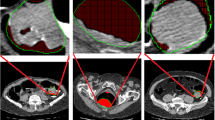

Differentiation of colon lesions according to underlying pathology, e.g., neoplastic and non-neoplastic lesions, is of fundamental importance for patient management. Image intensity-based textural features have been recognized as useful biomarker for the differentiation task. In this paper, we introduce texture features from higher-order images, i.e., gradient and curvature images, beyond the intensity image, for that task.

Based on the Haralick texture analysis method, we introduce a virtual pathological model to explore the utility of texture features from high-order differentiations, i.e., gradient and curvature, of the image intensity distribution. The texture features were validated on a database consisting of 148 colon lesions, of which 35 are non-neoplastic lesions, using the support vector machine classifier and the merit of area under the curve (AUC) of the receiver operating characteristics.

The AUC of classification was improved from 0.74 (using the image intensity alone) to 0.85 (by also considering the gradient and curvature images) in differentiating the neoplastic lesions from non-neoplastic ones, e.g., hyperplastic polyps from tubular adenomas, tubulovillous adenomas and adenocarcinomas.

The experimental results demonstrated that texture features from higher-order images can significantly improve the classification accuracy in pathological differentiation of colorectal lesions. The gain in differentiation capability shall increase the potential of computed tomography colonography for colorectal cancer screening by not only detecting polyps but also classifying them for optimal polyp management for the best outcome in personalized medicine.